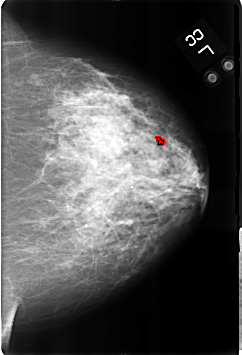

B_3174_1.LEFT_CC

LEFT_CC LINES 4608 PIXELS_PER_LINE 3136 BITS_PER_PIXEL 12 RESOLUTION 50 OVERLAY

FILE: B_3174_1.LEFT_CC.OVERLAY

TOTAL_ABNORMALITIES 1

ABNORMALITY 1

LESION_TYPE CALCIFICATION TYPE ROUND_AND_REGULAR-LUCENT_CENTER-DYSTROPHIC DISTRIBUTION DIFFUSELY_SCATTERED

ASSESSMENT 2

SUBTLETY 4

PATHOLOGY BENIGN_WITHOUT_CALLBACK

TOTAL_OUTLINES 1

BOUNDARY